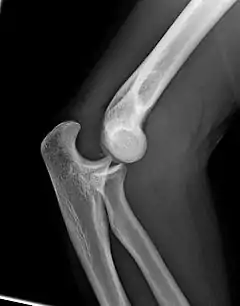

Codo humano izquierdo extendido

Codo humano izquierdo flexionado